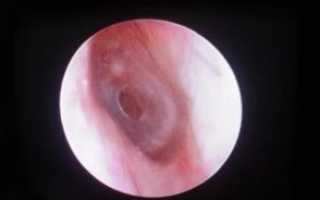

- Отоскопия. Исследуется сама барабанная перепонка и состояние краев дефекта (омозоленности, сращения с медиальной стенкой).

Разрыв тимпанической мембраны легко установить с помощью отоскопии — диагностической неинвазивной процедуры осмотра слухового прохода.

При разрыве барабанной перепонки отоскопия позволяет оценить состояние меатуса, собственно барабанной перепонки и, в ряде случаев, структур среднего уха.

Для ее проведения используют ушные воронки и лобный рефлектор или современный отоскоп, который совмещает в себе ушную воронку, источник света и увеличительный прибор.

Чтобы барабанная перепонка стала доступной для осмотра, необходимо предварительно очистить слуховой проход от серы, грязи, крови, выделений или инородного тела. При отоскопии определяются:

- усиление сосудистого рисунка при небольшом травмировании;

- кровоизлияния в мембрану при акустических травмах;

- видимые дефекты при значительных повреждениях;

- место разрыва с неровными краями, а также внутреннюю стенку барабанной полости;

- гематому тимпанической полости.